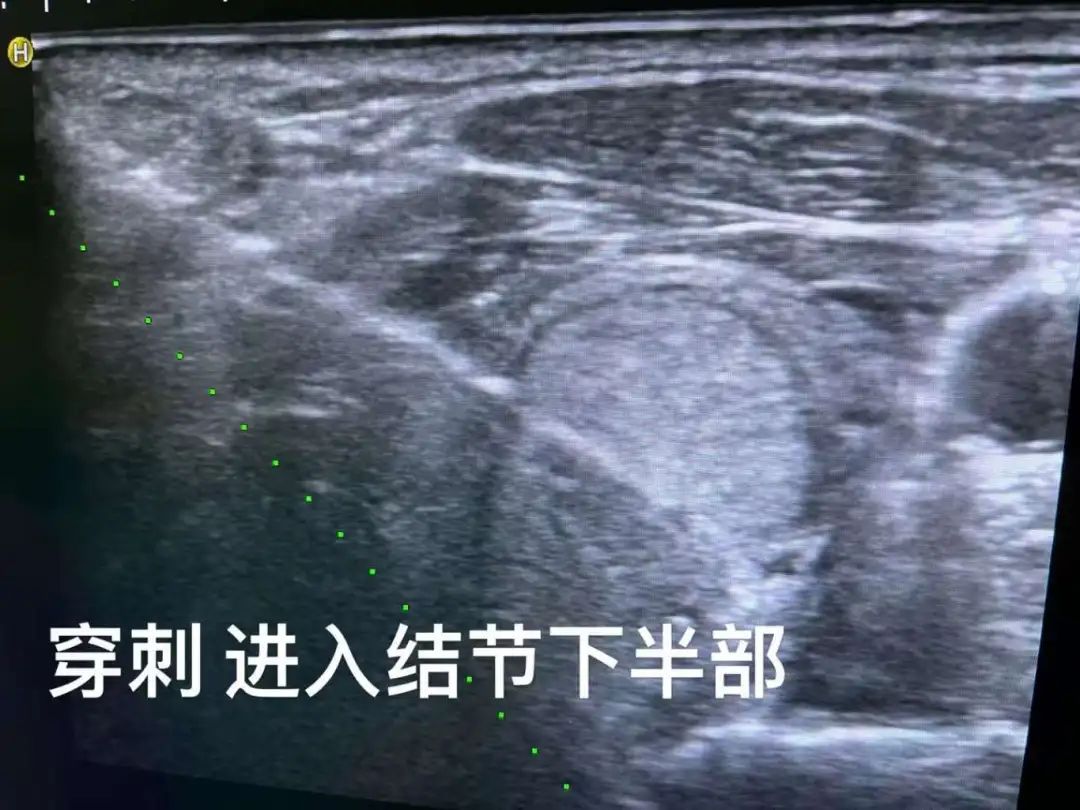

“这个甲状腺瘤比较大,血供也比较丰富,临近周边组织血管,手术有一定风险。但我们可以在超声可视化引导下,避开颈部丰富的神经及血管,将一根‘针’插到肿瘤内,用‘热’把肿瘤杀死。”这个“热”消融,也就是微波消融术,我们利用“移动消融“的方法,把大的肿瘤分成不同部分分别消融,像工匠雕刻一样,才能把边边角角都消融干净。

甲状腺瘤微波消融。像工匠雕刻一样,“移动消融“的方法,把大肿瘤分成不同部分分别消融。

超声引导下局部消融治疗甲状腺病变是近年来消融技术临床应用的研究热点,其以微创、安全、疗效确切等优势,为甲状腺疾病治疗带来了新发展。但局部消融技术起初应用于治疗甲状腺结节时,消融的方式是固定针消融,即取单点或多点多针对甲状腺肿瘤进行覆盖。

2008年Jeong等在甲状腺射频消融治疗中首先提出了“moving-shot technique”,即移动消融的方式,通过针尖移动形成多个大小不等的消融单位从而覆盖整个病灶,在后续临床实践中取得了良好的疗效。Lim等随访(49.4±13.6)个月,结节平均缩小率达到(93.4±11.7)%。相比之下,移动消融灵活性较高,消融单位大小可通过改变针尖移动的速率来调整。